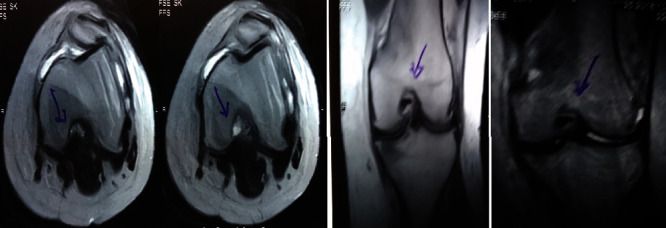

治疗后一个月进行随访。在第一次细胞治疗后,患者的疼痛明显减轻。第二次疗程后,她没有疼痛,并注意到运动范围有所改善。持续的物理治疗也观察到下肢肌肉力量的增加。从治疗开始(11个月前)到最后一次随访(4个月前),患者按照建议的饮食和基于运动的方案减重了11公斤。因此,她现在整体身体健康,能够更舒适地进行日常生活活动。表3显示治疗前后的MRI检查结果。人物的图1和的和图2显示半月板撕裂的治疗前和治疗后(1年后)图片。观察到损伤程度的改善图2。